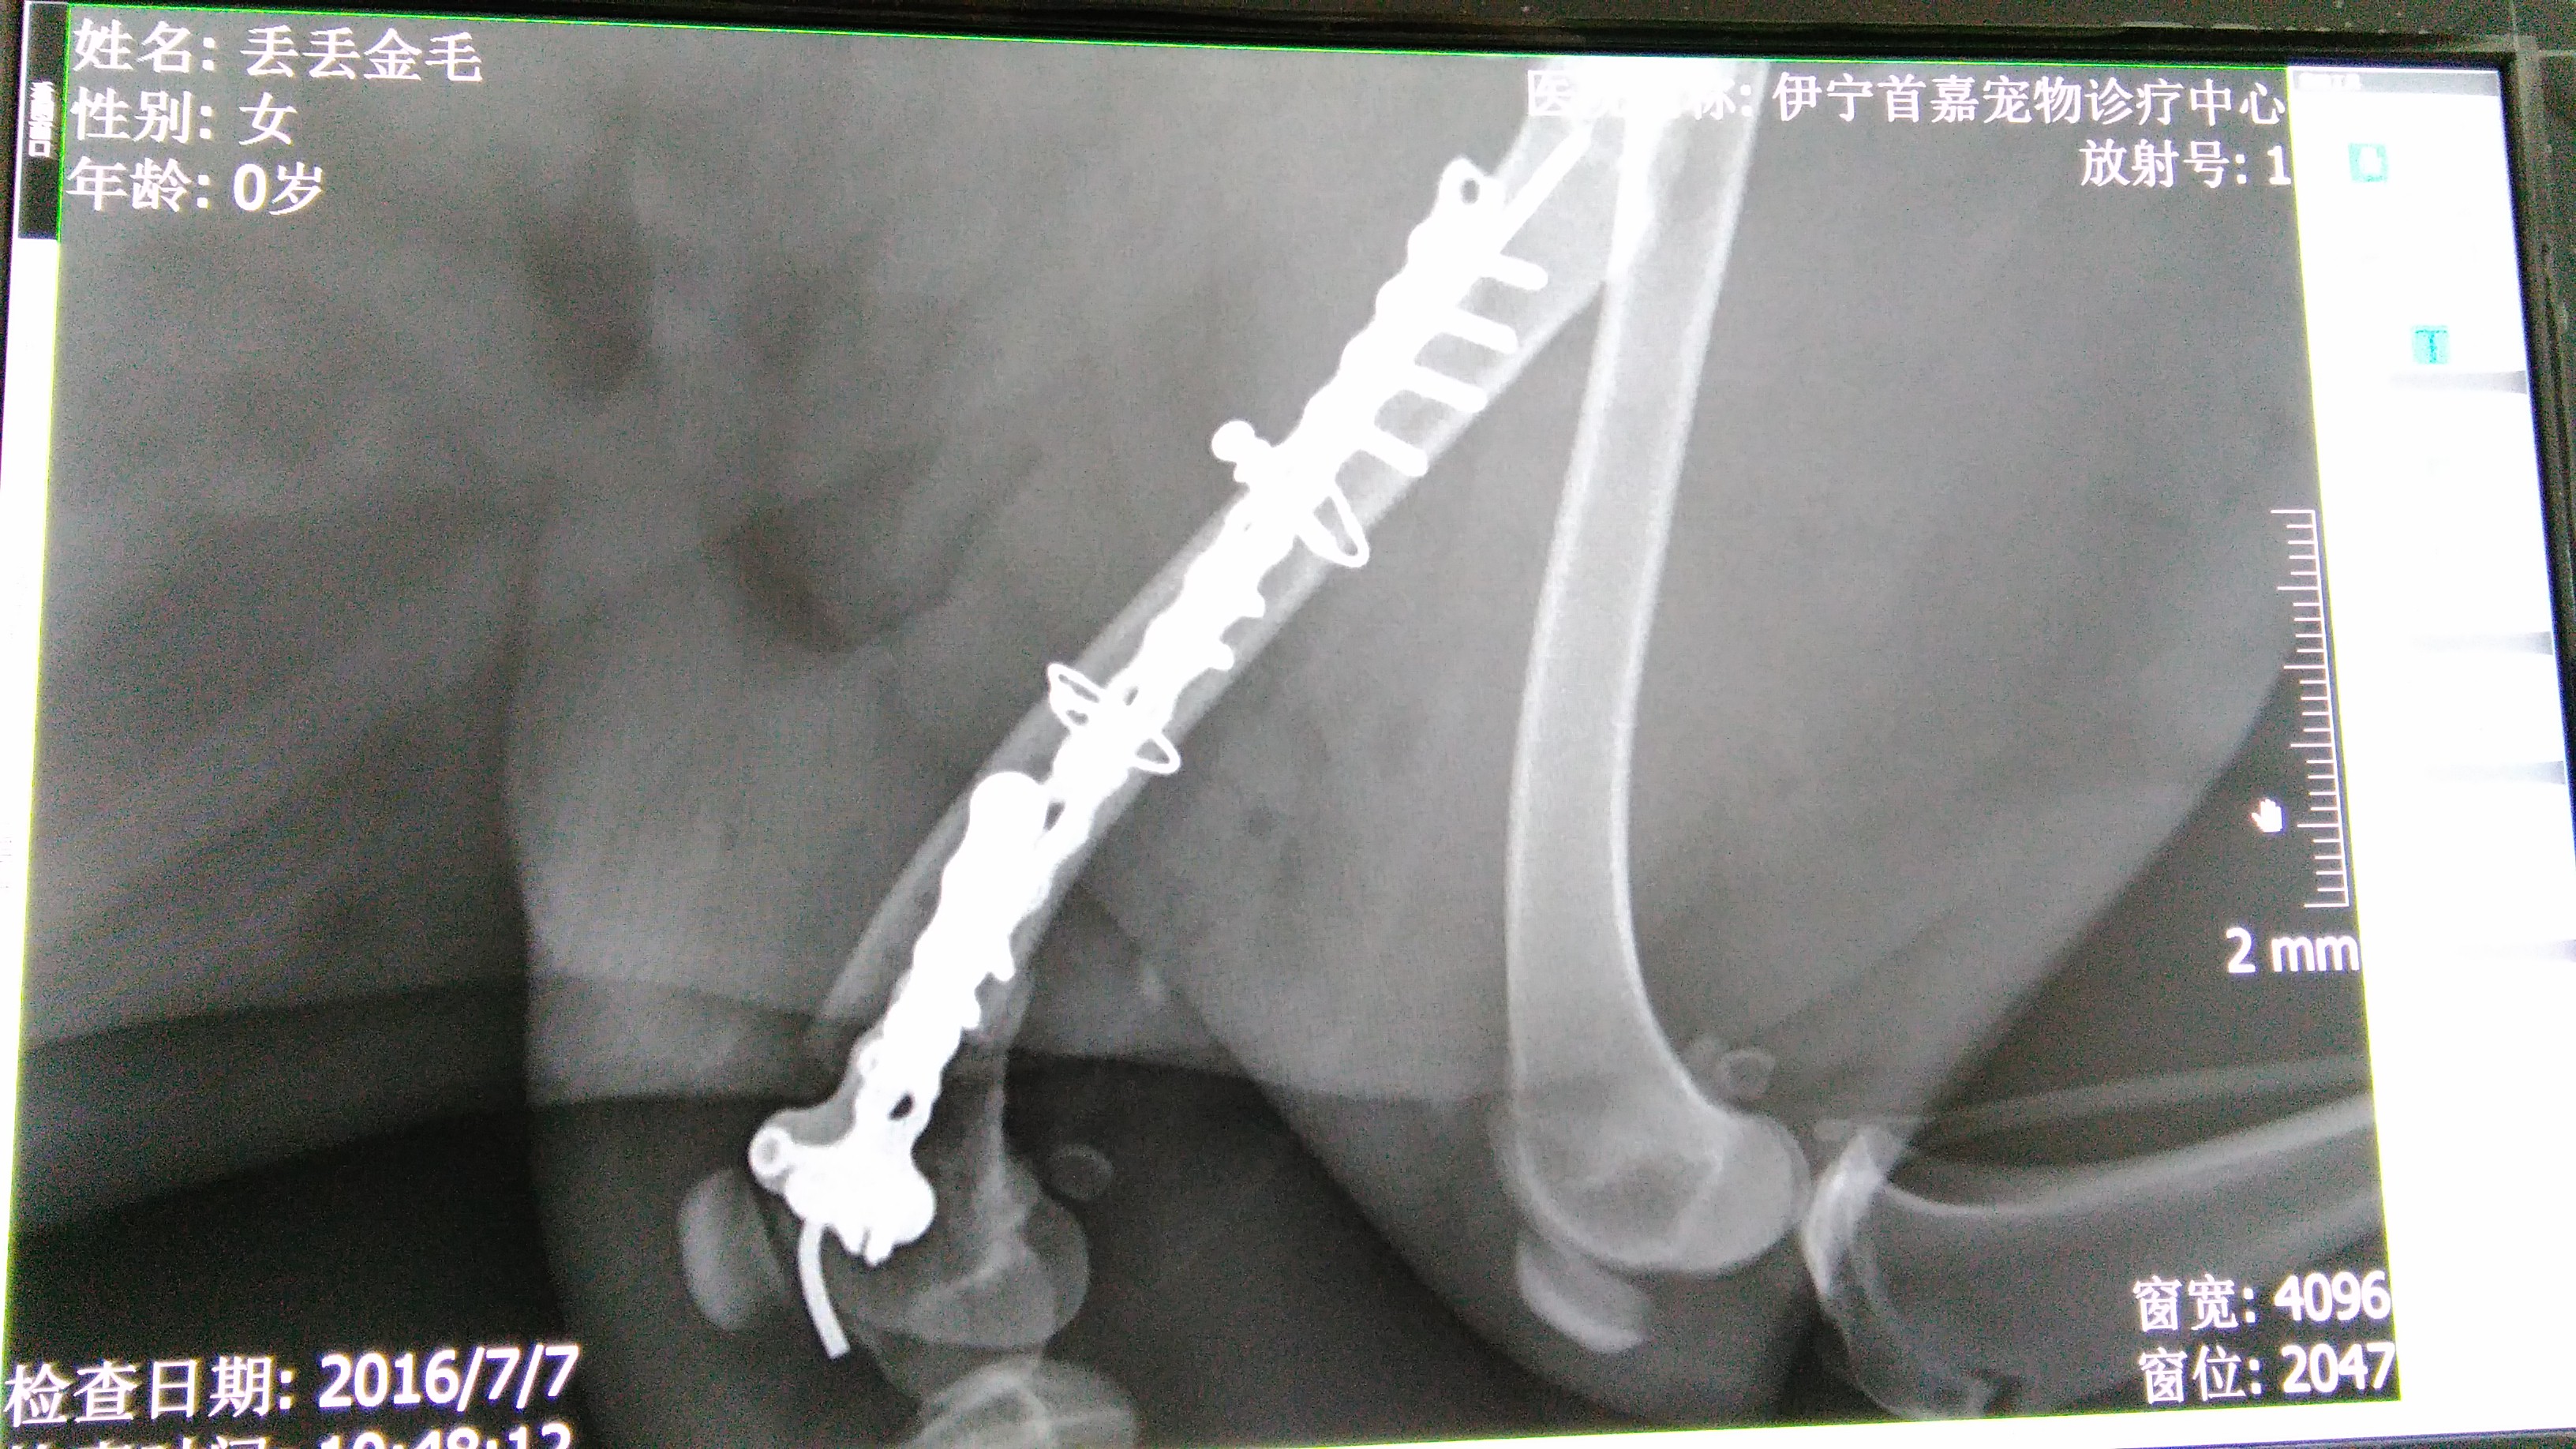

金毛犬,丢丢。于2016年6月24日晚车祸送到我院治疗,检查完之后,肝脏破裂出血,左后腿粉碎性骨折,断成三阶。第二天主人因经济问题放弃治疗,我院接手她,并有大量爱心人士捐款治疗。前期一直在调理修复肝脏和内出血治疗中,7月6号进行骨折内固定手术,手术中发现股骨断端撕裂膝关节并导致韧带断裂,手术修复并固定。经过一段时间调养,丢丢又可以走路。